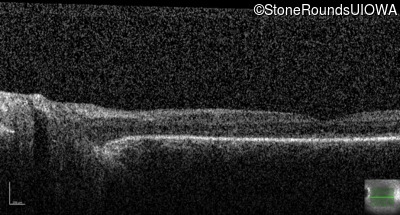

Optical Coherence Tomography - Right - Light Perception

Exemplar / OCT Stack